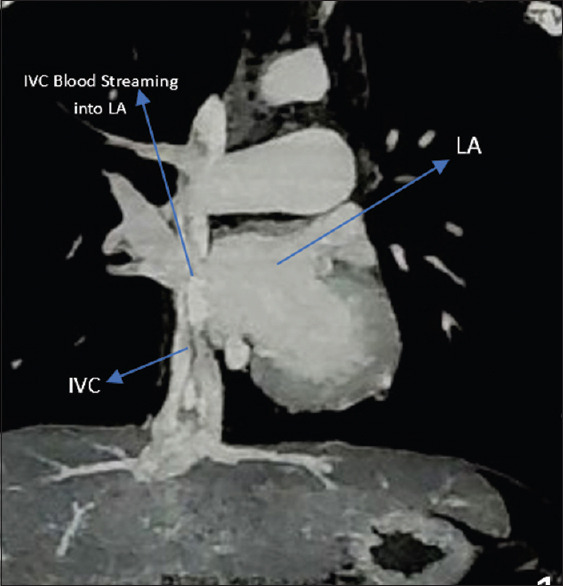

Residual defect after surgical closure of atrial septal defect is extremely uncommon. This communication reports four cases encountered in a tertiary care center during the last three decades. Clinical diagnosis was challenging, and the diverse presentations included acute ischemic stroke, cyanosis, and right ventricular volume overload. The morphology of the residual defects was complex, and multimodality imaging (transesophageal echocardiography, peripheral venous contrast studies, computed tomography, and balloon occlusion) enabled accurate recognition. Percutaneous device closure was feasible in one but required repeat surgery owing to unfavorable anatomy in the others. The communication focuses on difficulties in diagnosis and management.

Abstract Image